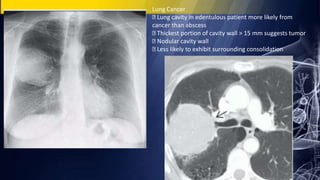

Lung Cancer

Lung cavity in edentulous patient more likely from

cancer than abscess

Thickest portion of cavity wall > 15 mm suggests tumor

Nodular cavity wall

Less likely to exhibit surrounding consolidation